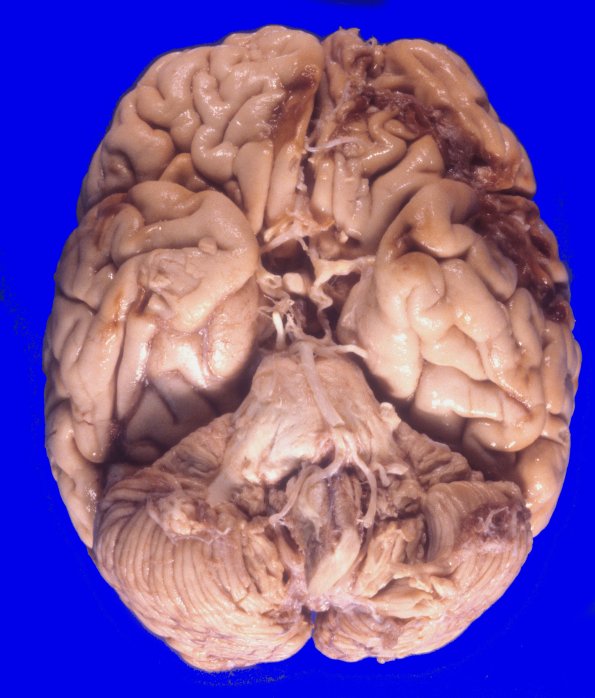

17A2 Trauma, Baseball bat (Case 17) 1

17A2 In addition, the ventral aspect shows more typical patterns of contusion involving the orbital frontal cortices.